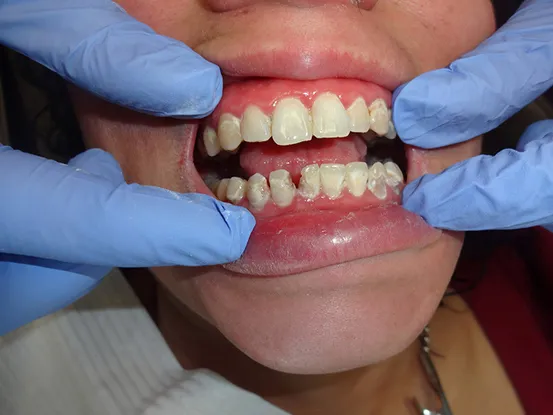

Case 7

38 year old female with extensive cervical caries from a high sugar diet and poor oral hygiene. 12 units of porcelain crowns and composite fillings to restore form and function followed by frequent recall visits